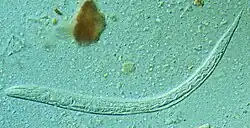

| First stage larva (L1) of S. stercoralis | |